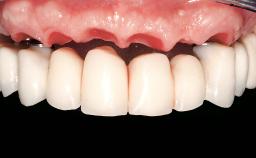

Prosthesis Type | FDP |